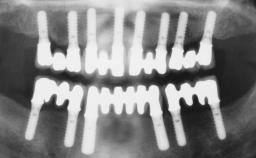

A healthy 31-year-old female patient presented with a failing maxillary left lateral incisor crown. The crown regularly loosened, and the remaining tooth was neither restorable nor rational to treat. The patient had a high smile line, a medium soft tissue biotype with a compromised mesial papilla (shorter than the contralateral one), and a horizontal scar in the buccal soft tissue as a result of past periapical surgery.

| Timing of placement | Immediate Placement (extraction sockets) (Type I) |

| Radicular morphology | Uniradicular |

| Available apical bone to achieve primary stability | Sufficient height ( ≥ 4 mm) and width (> 2 mm around apex of planned implant) |

| Socket walls | Intact |

| Thickness of buccal wall | less than 2 mm |

| Anticipated residual defect after implant placement | 2 mm or less |